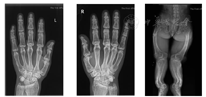

患者入院后查血磷0.43 mmol/L,低于正常范围;碱性磷酸酶126 U/L,正常范围上限;25羟维生素(25OHD)10.1 ng/ml低于正常范围;钙2.16 mmol/L,正常范围;甲状旁腺激素123 ng/L,高于正常范围;肌酐31 μmol/L、24 h尿磷13.95 mmol/L,低于正常范围;24 h尿钙5.22 mmol/24 h,正常范围(表1)。查骨密度示:腰椎L1~2低骨量,L3~4骨质疏松,股骨颈端、Wards三角低骨量,大粗隆骨质疏松,查双手及双下肢X线所见双手多发掌指骨骨质密度减低,呈膨胀性改变,部分骨端边缘骨质增生。双下肢形态扭曲,骨盆诸骨及双下肢构成骨骨密度减低,呈膨胀性改变;双股骨、右腓骨及左胫腓骨见骨质不连续,断端骨质硬化发白,右腓骨上段不规则形骨性突起,背离关节生长(图3)。基因检测结果:先证者的X染色体上内肽酶同源磷调节基因发现染色体位点22132610突变,致使核苷酸c.1208G>A,致使氨基酸p.W403X改变(图4)。